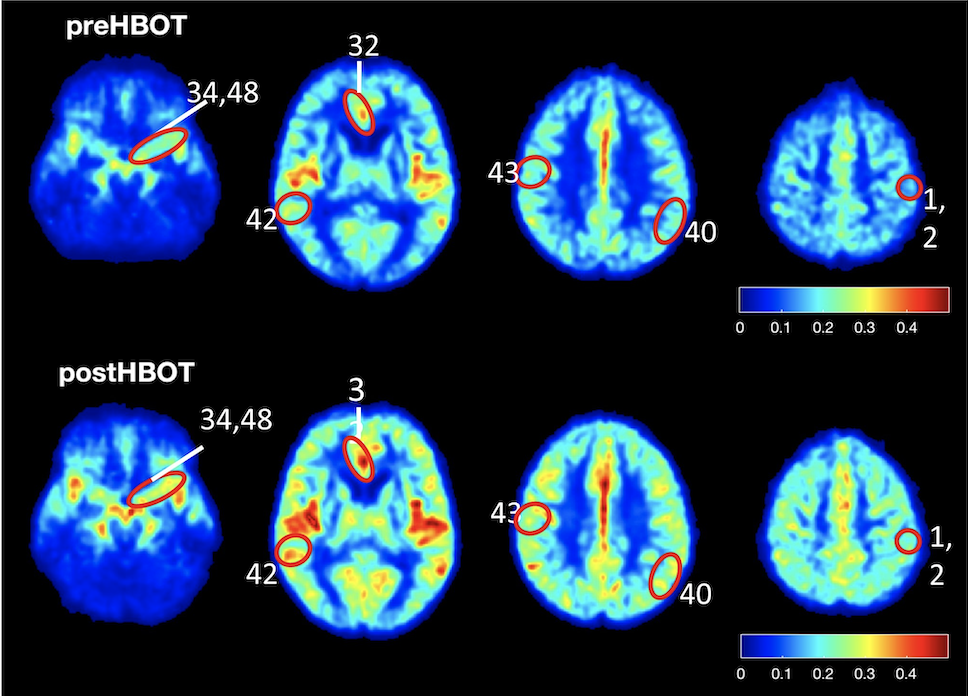

À l’étape suivante, les effets du traitement ont été examinés sur des personnes de plus de 65 ans présentant un déclin cognitif, en particulier une perte importante de mémoire, étape précédant la maladie d’Alzheimer et la démence. La thérapie comprenait une série de 60 séances en chambre de pression sur une période de 90 jours. Les effets sur le cerveau ont été évalués par IRM à haute résolution. Le protocole de traitement hyperbare a donné lieu à une augmentation du flux sanguin vers le cerveau de l’ordre de 16 % à 23 %, une amélioration de la mémoire de 16,5% en moyenne, une amélioration des capacités d’attention de 6% en moyenne, et de la vitesse de traitement de l’information de 10,3%.

1. Images IRM montrant l’amélioration du flux sanguin après le traitement en chambre de pression. Les zones présentant une amélioration de la circulation sanguine sont marquées par des cercles rouges. (Crédit : Extrait de l’article)